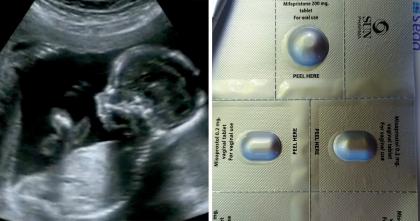

Відповідно до рішення Вашингтонського управління з контролю за продуктами і ліками (FDA), небезпечні протизаплідні таблетки Opill виробництва ірландського концерну Perrigo тепер продаватимуться без рецепта і без вікових обмежень.

Як пояснює Келвін Фрайбурґер з LifeSiteNews, “контрацептиви на основі прогестину, такі як Opill і Plan B, широко рекламуються як альтернатива абортам, оскільки вони нібито запобігають вагітності, а не переривають її”, але “вони насправді мають абортивний потенціал, а те, чи запобігають вони зачаттю чи імплантації залежить від того, коли їх приймають з огляду на жіночий цикл”.

Аби обійти ці “труднощі”, FDA вирішило змінити правила класифікації цих “препаратів” так, аби їх більше не називали абортивними, а просто протизаплідними.